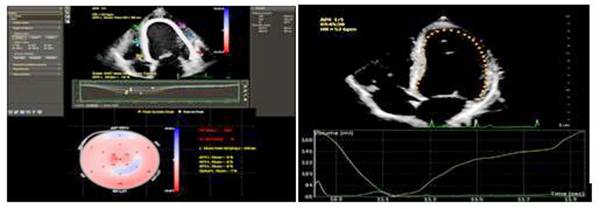

1、 自动心肌运动定量技术

依据选择的心脏切面自动描记相应心肌节段,进而测量整体和节段功能并生成18节段牛眼图,同时获得患者的左心室局部及整体应变值,对冠心病和心肌病患者左室壁运动的评估更为精准。